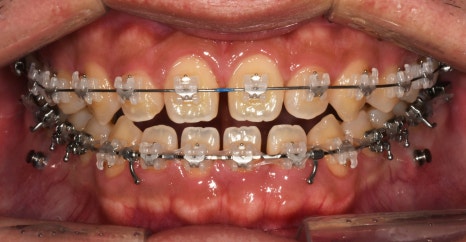

오늘 살펴볼 세라믹치과의

반대교합 치아교정전후 사례는

반대교합, 아래턱 돌출, 비발치 교정으로

진행한 증례입니다.

치료계획

🔎 교정시작 나이 : 24세

🔎 교정시작 이유 : 반대교합, 치아 벌어짐

🔎 교정 소요일 : 약 1년 2개월

앞니 반대교합

아래턱 돌출

치아 벌어짐

또한 치아배열도 좋지 않았고

비대칭이 함께 있는 상태였습니다.

-부정교합 개선을 위한 '비발치 교정'

(예상 기간 24개월)

교정과정

한눈에 보기

1 / 2

3 / 4